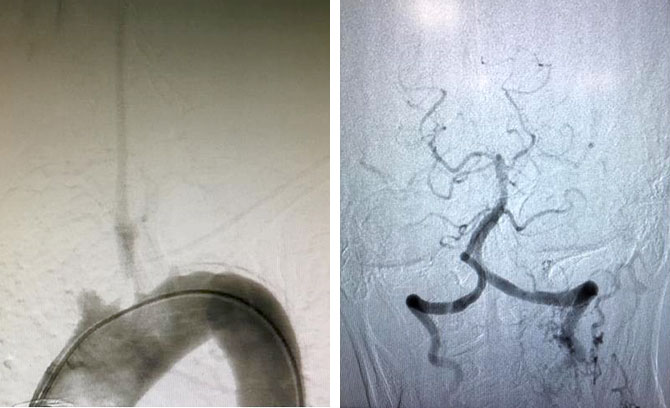

左图:术前造影显示右侧头臂干、左侧锁骨下动脉闭塞,左侧颈总动脉狭窄只剩一丝血流。

右图:术后脑血管显影,脑组织再次充满血流。

当血管开通后,再次做脑血管造影时,可以清晰的看到谢阿姨所有的脑组织再次充满血流。看到这一幕,所有的手术医生忘记了疲劳,从心底发出欢呼,既是对手术成功的欢呼,更是为病人再获新生而欢呼。